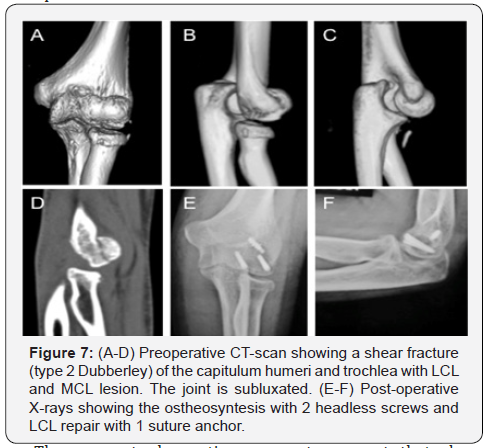

Humeral shear fractures are rare injuries that involve the capitellum and trochlea and account for 1 % of all elbow fractures and 6 % of distal humeral fractures; the incidence of such fractures is higher in women than in men because the former suffer from osteoporosis to a greater extent than the latter [111]. The mechanism of injury usually consists of a fall on an outstretched arm, which results in direct axial and valgus compression transmitted to the capitellum by the radial head [112]. Several classifications have been proposed for this kind of fracture, the most widely used being that by Bryan- Morrey. In 2006, Dubberley et al. [113] classified humeral shear fractures according to 3 different types: type 1, which involves the capitellum with or without the lateral trochlear ridge; type 2, a fracture of the capitellum and trochlea as one piece; type 3, fractures of both the capitellum and the trochlea as separate pieces. These fractures are further divided depending on the absence (A) or presence (B) of posterior condylar comminution given that osteosynthesis may be more challenging in the latter case.

Coronal shear fractures usually occur in isolation with a stable elbow, but may be involved in a more complex elbow injury with other osseous and soft-tissue constraint lesions. Indeed, an associated radial head fracture has been observed in as many as 30% of cases [111,113-116] while an association with an olecranon or coronoid fracture is rarer [117-119]. Ruchelsmann reported that 4 out of 5 associated radial head fractures in his series occurred in type IV fractures, according to the Bryan-Morrey classification [119]. Some studies have observed LCL lesions in up to 40% of cases [113-116]. In their series of 18 patients, Mighel et al. [116] found that a LCL injury was more often associated with injuries involving the capitellum and trochlea as one piece than with isolated fractures of the capitellum. In another series of 15 patients who sustained humeral shear fractures and were treated with ORIF and hinged external fixation, Giannicola et al. [120] reported 4 cases who had an elbow dislocation associated with both collateral ligament disruption, while another 4 cases had a MCL tear.

These recent observations seem to suggest that shear fractures associated with elbow dislocation or lateral and medial collateral ligament tears may represent a pattern of CEI according to which bone failure occurs on the humeral rather than on the ulnar or radial side. This is the reason why we decided to include this type of lesion in CEI even though no consensus has yet been reached on this issue. A distinction should be made between this type of injury and monocondylar fractures of the distal humerus, which are unstable owing to the fragment displacement which includes the collateral ligament that remains intact. In the latter case, condylar ORIF directly restores the stability of the elbow, whereas ligament reconstruction is required after ORIF when shear fractures are associated with ligament lesions; in such cases, the pathoanatomical finding of a soft tissue constraint lesion is, in our experience, comparable to that observed in other CEI patterns [120].

In view of these considerations, the same therapeutic algorithm of CEI should be applied to this type of injury. In brief, correct surgical treatment consists in performing ORIF with headless screws and ligament repair (Figure 7), as has also been advocated by other authors [121]. There is as yet no consensus on the optimal method of fixation for these challenging fractures, though headless compression screws are widely adopted. Indeed, one biomechanical study has shown that the placement of headless compression screws in an anterior-posterior fashion is superior to placing cancellous screws in a posterior-to-anterior fashion [122]. Furthermore, placing screws in an anterior-toposterior fashion does not entail disrupting the posterior soft tissues, and thus helps to preserve the distal humeral blood supply.